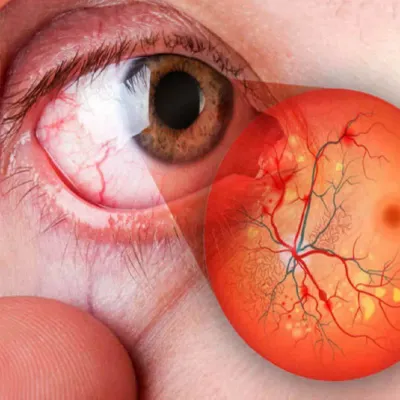

LÁSER DE RETINA

LÁSER DE RETINA

Láser de última generación para tratar agujeros y desgarros de retina, retinopatía diabética, oclusiones vasculares retinianas, entre otras.

CIRUGÍA DE RETINA

CIRUGÍA DE RETINA

Cirugía para desprendimiento de retina, hemorragia vítrea, retinopatía diabética, agujero macular con la mejor tecnología.

RETINOPATÍA DIABÉTICA

RETINOPATÍA DIABÉTICA

¿Que es la Retinopatía Diabética?

RETINOPATÍA DIABÉTICA

¿Qué es la retinopatía diabética?

La retinopatía diabética es una complicación de la diabetes que afecta a los vasos sanguíneos de la retina, la capa sensible a la luz en la parte posterior del ojo. Si no se trata, puede causar ceguera.